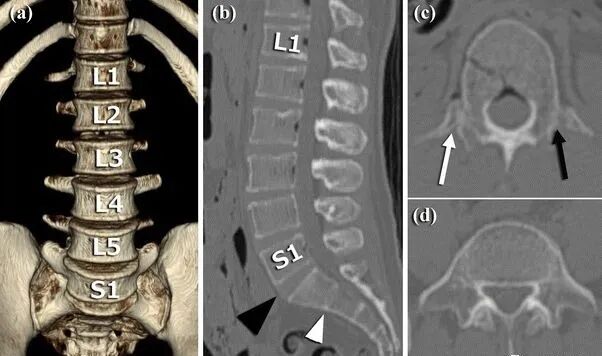

1984年,Castellvi 提出LSTV分类系统将移行椎分为Ⅰ-Ⅳ型。

Ia型(单侧)和Ib型(双侧):横突肥大宽度超过19mm

IIa型(单侧)和IIb型(双侧):横突与骶骨相接触形成假关节

IIIa型(单侧)和IIIb型(双侧),横突与骶骨发生骨性融合

IV型:一侧横突与骶骨形成假关节,另一侧形成骨性融合

目前,腰骶移行椎以 Castellvi 的分类方法最为常用。其主要根据横突形态及其与骶骨、髂骨是否融合或形成假关节而分为 4 型,Ⅰ、Ⅱ、Ⅲ型又根据单、双侧分为A、B两个亚型。

正常I型:主要为腰5横突发育不良,横突宽度大于19mm,并将其分为两个亚型Ia(单侧横突发育不良)或Ib(双侧横突发育不良)

L5 右侧横突肥大,为 Ⅰa 型

L5 双侧横突肥大,为Ⅰb 型

II型:表现为不完全的腰椎骶化,具有增宽的横突,并且和骶骨形成假关节,并将其分为两个亚型IIa(单侧关节形成)或IIb(双侧关节形成)

L5 左侧横突肥大,假关节形成,为 Ⅱa 型

L5 双侧横突肥大,假关节形成,为 Ⅱb 型

III型:单侧(IIIa)或双侧(IIIb)腰椎完全骶化,腰5横突与骶骨完全骨性融合

L5 右侧横突肥大与骶骨发生骨性融合,为 Ⅲa 型

L5 双侧横突与骶骨骨性融合,为 Ⅲb 型IV型:一侧为II型即腰5横突与骶骨形成假关节,对侧为III型即腰5横突与骶骨形成骨性融合

IV 型即混合型:L5 双侧横突肥大,一侧与骶骨相接触为Ⅱ型表现,另一侧与骶骨形成骨性融合为Ⅲ型移行椎一般不引起症状,但是这种畸形可影响脊柱的稳定并逐渐产生症状,移行椎较正常椎体潜在着更多不稳。由于负重及运动不平衡,而引起腰痛。